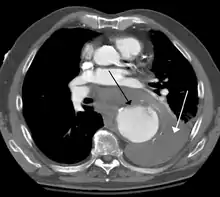

Diagnosis

Thoracic aortic aneurysm is defined as a cross-sectional diameter exceeding the following cutoff:

- 4.5 cm in the United States[7]

- 4.0 cm in South Korea[8]

A diameter of 3.5 cm is generally considered dilated.[7] However, average values vary with age and size of the reference population, as well as different segments of the aorta.